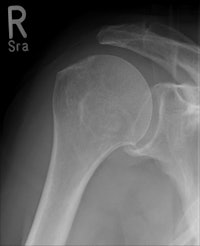

Data from 474 CR skeletal exams were collected; the CR cassette was then traded out for the wireless flat-panel DRX-1 detector to acquire an identical mix of 467 skeletal x-ray procedures. More than 50 patients were examined for each of nine types of inpatient and outpatient skeletal studies performed from January to June 2010.

Lehnert and colleagues also found that image quality also significantly improved in the shift from skeletal CR to DRX-1. Those results will be described in a separate study.